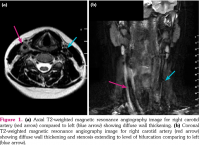

A 15-year-old girl was admitted to our clinic with dyspeptic complaints, diarrhea for two weeks, and weight loss. Her prenatal, natal, and postnatal history was uneventful. Her family history was unremarkable. Physical examination including growth parameters and pulses were in normal limits. Laboratory data revealed elevation of inflammatory markers. The upper endoscopy and colonoscopy presented multiple patchy and longitudinal mucosal aphthous ulcerations and cobblestone areas. Histopathological examination showed an increase of lamina propria cellularity, basal lymphoid aggregates, and epithelioid granuloma as well as crypt abscess formation. Clinical and histopathological findings were consistent with CD. The patient was initially treated with 2 mg/kg/day oral methylprednisolone. Azathioprine was added to corticosteroid therapy in follow-up. The corticosteroid therapy was tapered by the remission in third week. Over the course of two months, disease activity was unapparent with normal acute phase reactants. At the eighth month follow-up, acute phase indicators started to increase (erythrocyte sedimentation rate: 80 mm/hour, C-reactive protein: 92 mg/dL) in routine controls without any symptoms. All of the results were in normal ranges for the complete blood count, autoimmune markers, and endoscopic findings excluding disease activity. The patient had constitutional symptoms with unilateral neck pain with widespread sensitivity. Neck ultrasound revealed a stenosis of the right carotid artery. The magnetic resonance angiography imaging for right carotid artery showed diffuse wall thickening and 30-40% stenosis extending to the level of bifurcation (Figure 1). Clinical and laboratory features were consistent with TA. A written informed consent was obtained from the ethics committee and the parents of the patient.